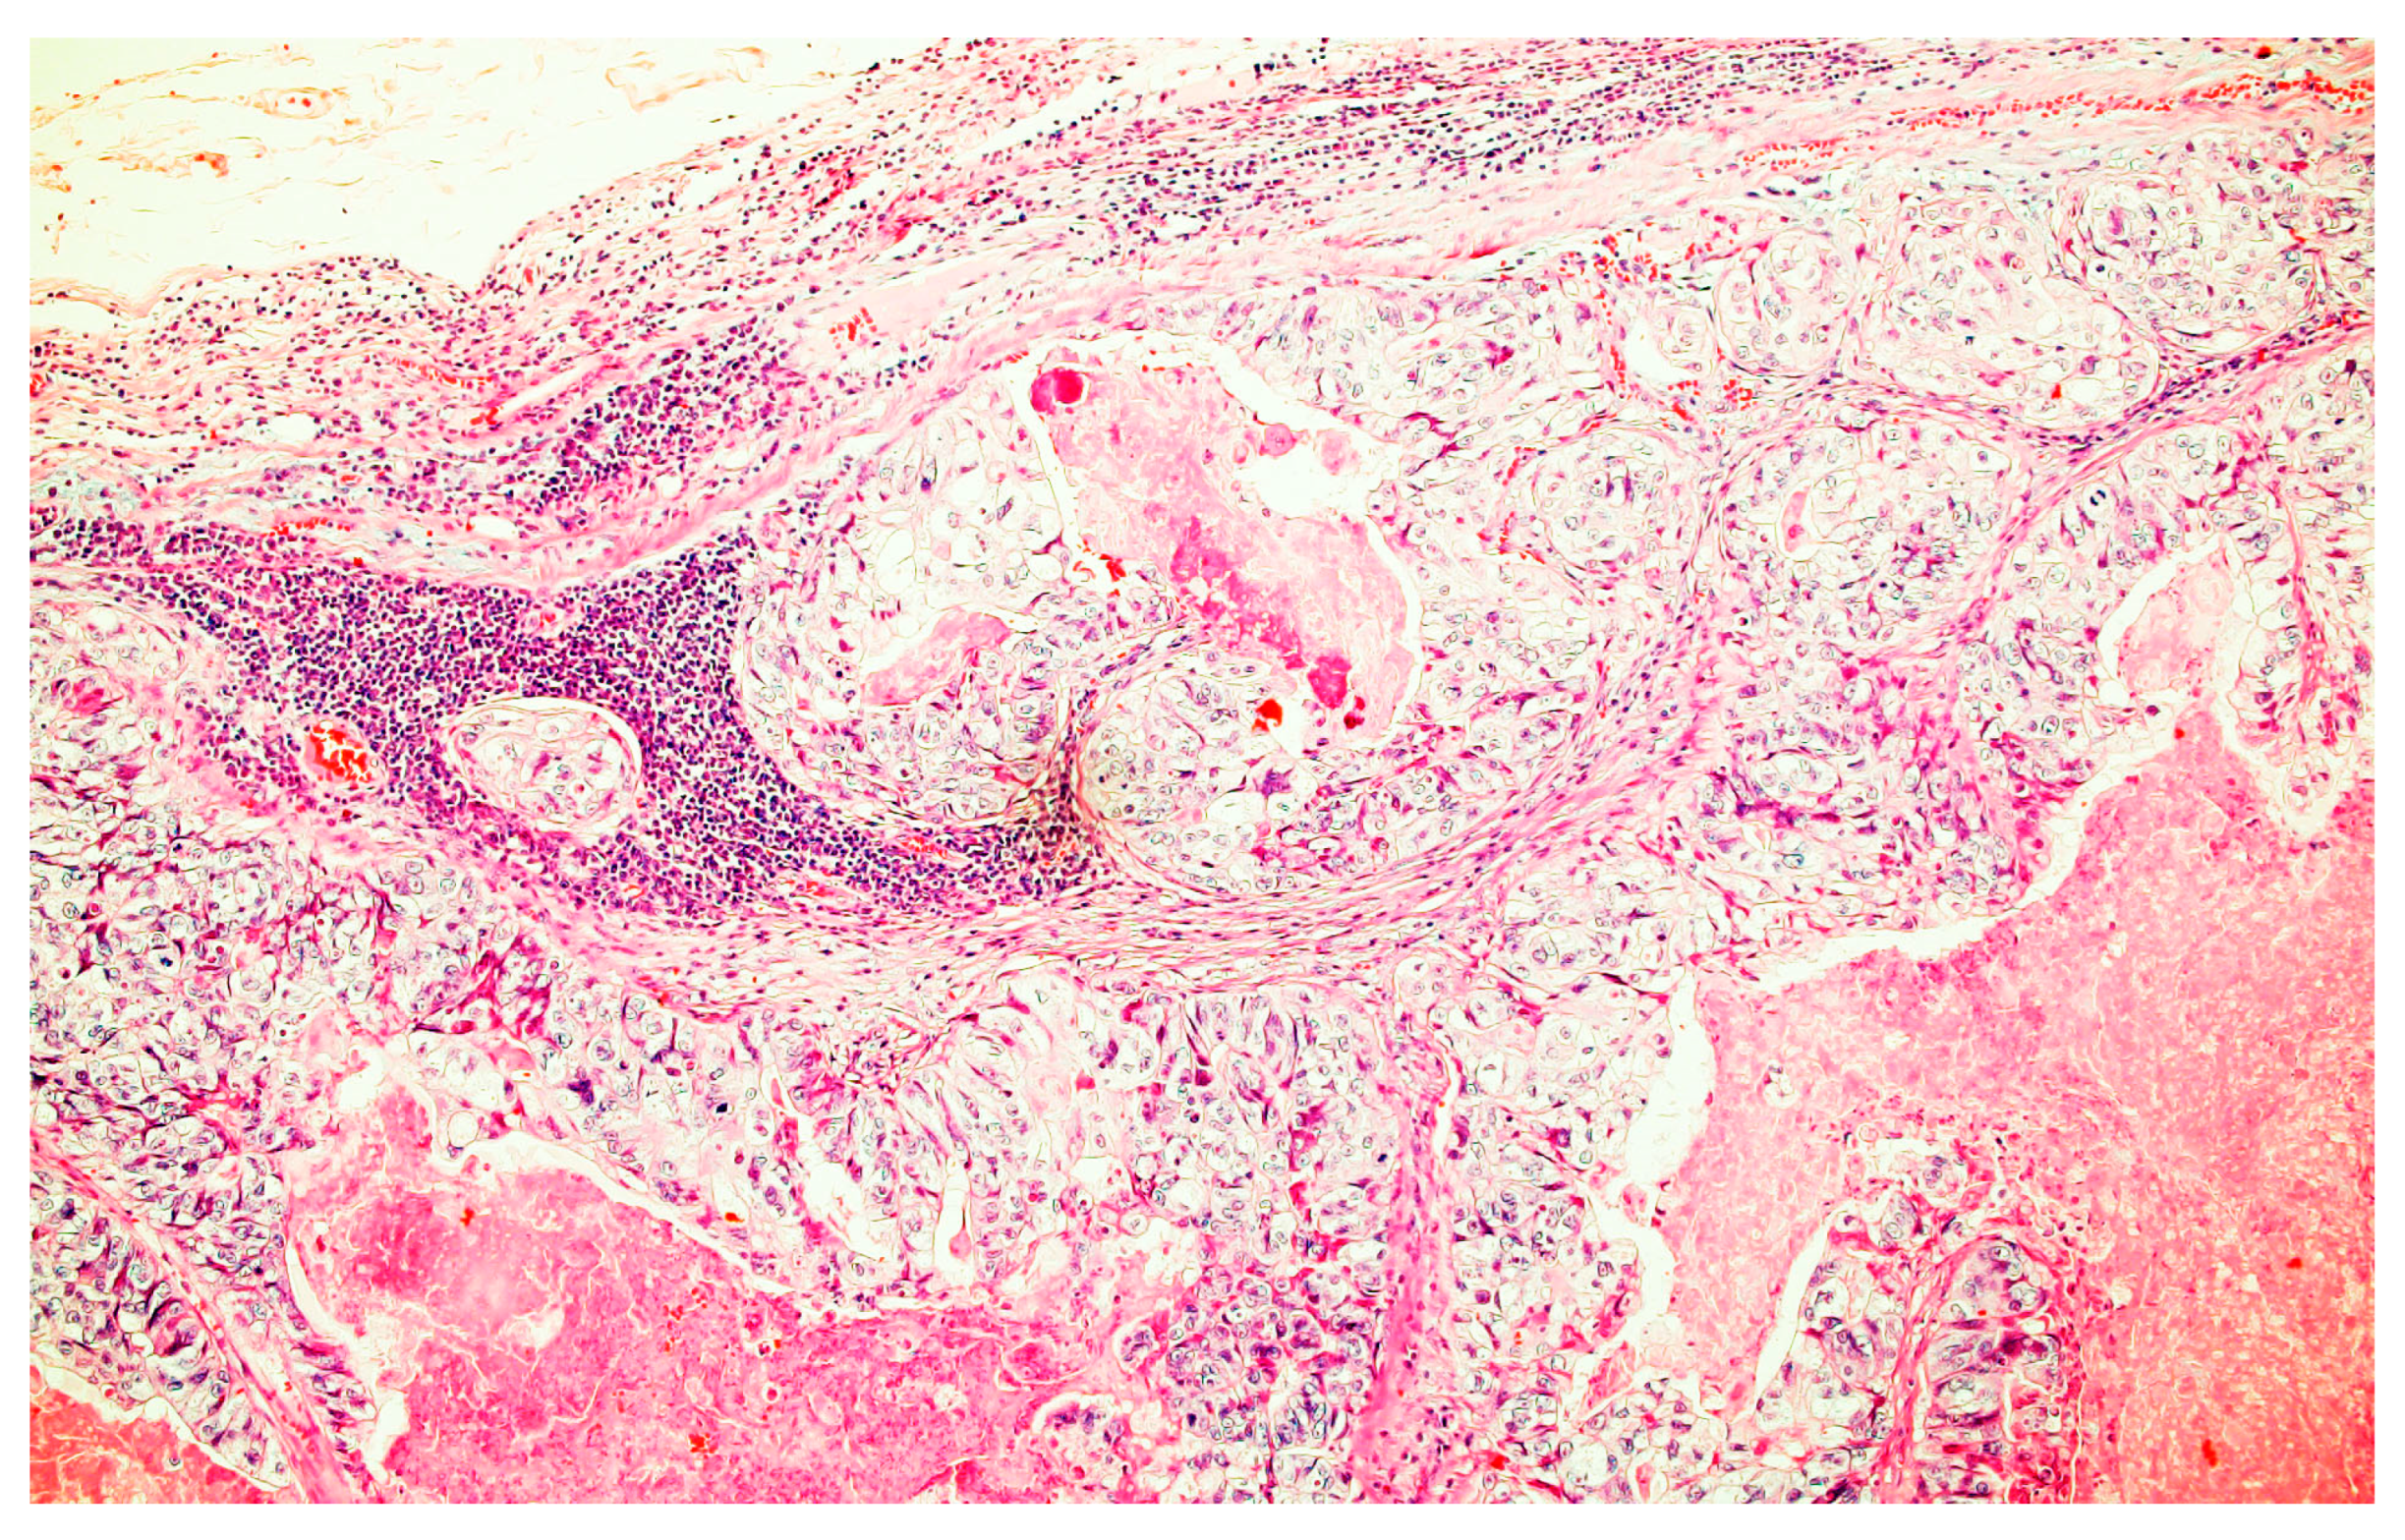

2.1. Case Report